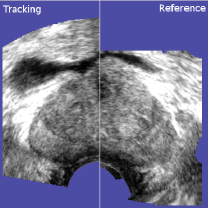

A comparison of the mean decile TRE of rigid and elastic registration was carried out to evaluate the clinical relevance of deformation estimation, see Fig. 17. Elastic registration improves TRE in all deciles about at least one third. In absolute values, it yields the strongest benefit in the worst decile, where the average error is decreased by 1 mm to 2 mm. The error curve of rigid registration indicates that the gland is barely deformed in the majority of the volumes that were analyzed. However, in about 20%percent\% to 30%percent\% of the volumes stronger deformations can be observed that can be reduced with elastic registration. The cross correlation between the TRE and the fiducial distance from the transducer is -0.09 for rigid registration, i.e. these two variables are uncorrelated. The cross correlation between the TRE and the fiducial distance from the prostate center is 0.17 for rigid registration, i.e. the error at the capsule is of similar extent than the error at the center. The cross correlation between the TRE and the fiducial distance to the needle tip is 0.02, and between the TRE and the fiducial distance to the entire needle trajectory is 0.0. We therefore did not measure significantly stronger errors near the needle than elsewhere. This observation has to be, however, taken with care since it is possible that including all fiducials to measure a local phenomenon (the volume of the needle is very small compared to the volume of the prostate), together with the sparse number of fiducials per volume, might compromise the statistical power of this particular test. A visual illustration of the deformation estimation is given in Fig. 18.

Refer to caption

Figure 18: Rigid vs. Elastic. Fig. (a) and (c) show typical rigid registration results, the left half of each image showing the tracking image, and the right half showing the reference. In both cases, different probe pressure was applied when the volumes were acquired. The non-linear compression cannot be corrected by the rigid registration and local mismatches subsist in particular near the probe head. Fig. (b) and (d) show the result of the deformation estimation, which corrects the local errors.